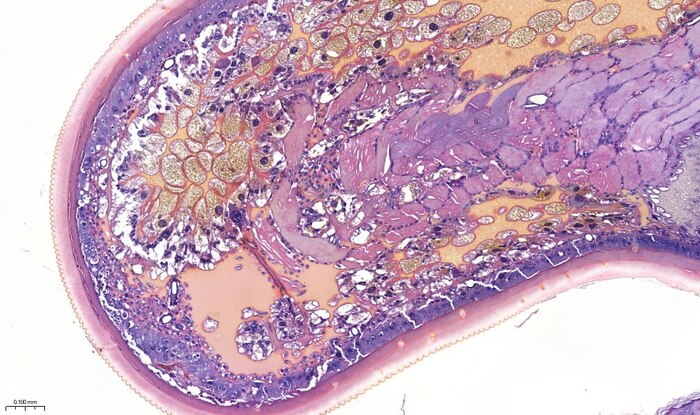

Угадайте опухоль, господа!

Ни за что не угадаете!

Дорогие коллеги, доброе утро.

Удивительно, но это второй такой случай в нашей практике.

Первый был довольно давно и тогда направительный диагноз звучал как «бустрорастущая меланома».

В этот раз обошлись папилломой грудной клетки.

В прошлый раз с такой «опухолью» столкнулся Станислав, в этот раз мне это прислал наш доктор – Д.К. Корнюшин, за что ему мои благодарности.

Да, коллеги – это клещ. Иксодовый. Может как-то еще сложнее называется – я не разбираюсь в них. Кто-то сказал, что это самка – не знаю половых признаков клещей, может и здесь вы правы.

По поводу радикальности метода удаления ничего сказать не могу. В оправдание ситуации могу предположить, что степень выраженности изменений в окружающих тканях подвигла на такой метод лечения. Впрочем, диагноз направления мог бы быть иным, учитывая макроскопическую картину.